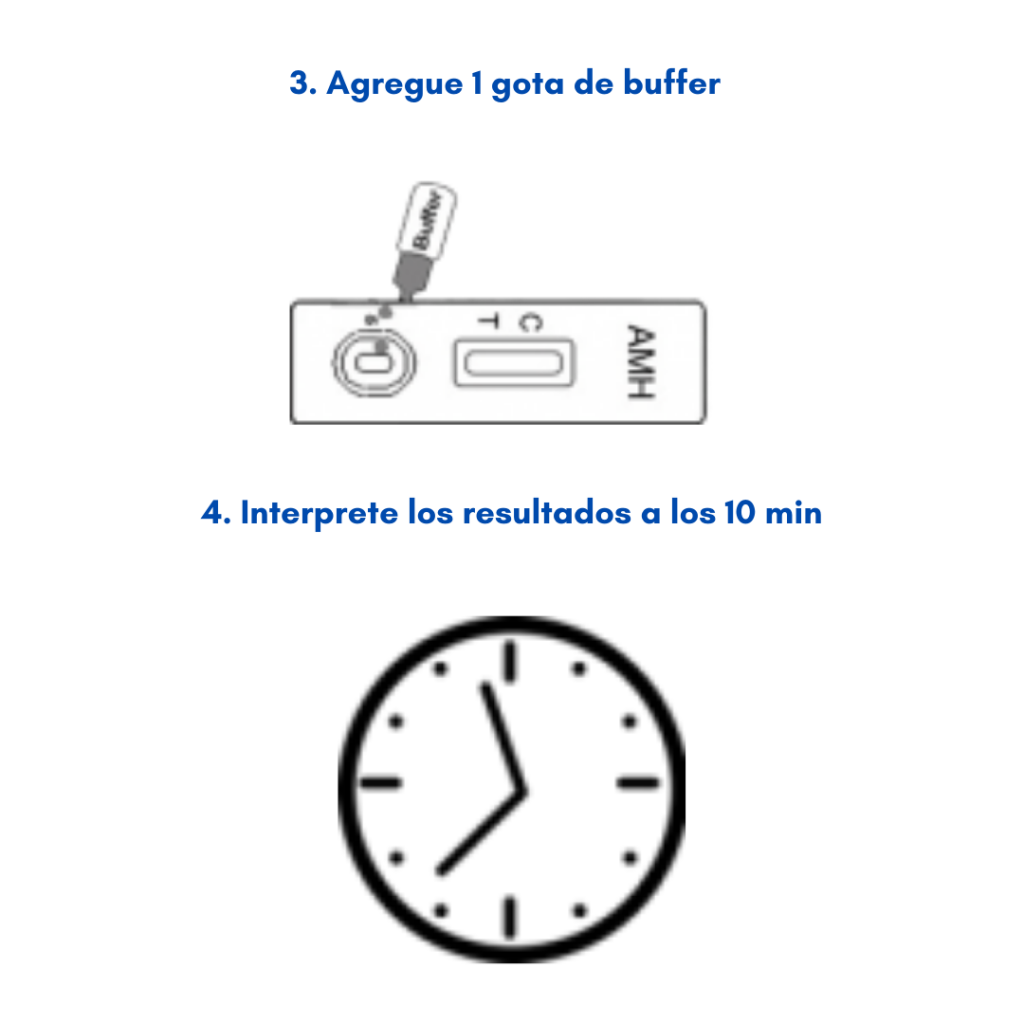

Solo necesitas de tres gotas de sangre extraídas de tu dedo, o dos gotas de suero o plasma, colocar la muestra recolectada en el casete de la prueba, agregar una gota de buffer y esperar 10 minutos para interpretar los resultados. Así de rápido!

A continuación te demostramos como hacerlo de manera rápida.

Si la Prueba Rápida de AMH arroja un resultado positivo de acuerdo con las normativas internacionales se debe hacer una prueba de laboratorio confirmatoria de dicho resultado, es importante recordar que las Pruebas Rápidas son auxiliares de diagnóstico para obtener un resultado, rápido y seguro desde el lugar que te encuentres.